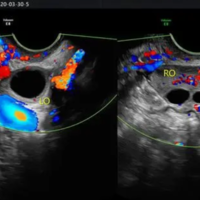

为什么试管促排后只有一侧卵巢有优势卵泡呢?

问题描述:我今年35岁,和丈夫结婚5年了,我们多次同房无果,所以就去做了试管婴儿技术,我在促排期间吃了很多药,现在已经一个月过去了,我去医院监测卵泡的时候发现,我的卵巢只有一侧有优势卵泡,我有点迷茫,想问问大家,为什么在促排后,我只有一侧卵巢有优势卵泡呢?最佳回答:这种现象可能是正常的,但也有可能是多囊卵巢综合征,内分泌紊乱等因素引起的,卵巢排卵是左右交替进行的,有时一侧卵巢可能较为活跃,所以会产...